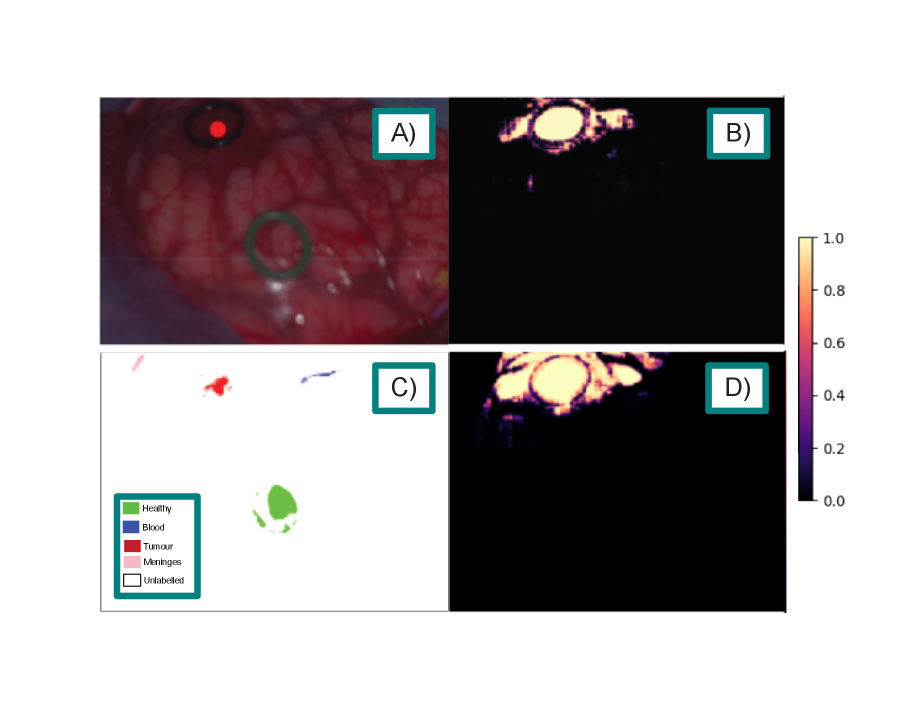

Qualitative comparisons further highlight the advantages of SAMSA2 over fine-tuned RGB baselines. On the HIB dataset (fig. 2), both SAMSA2-Large and SAM2-Large-FT correctly localise the tumour, but SAMSA2 provides a more refined boundary, offering greater clinical interpretability. On the SB-X and SB-H datasets (figs. 3 and 4), both methods capture the tumour within the marked region, yet SAMSA2 extends its prediction beyond the visible margins, suggesting the potential to reveal subsurface infiltration that may not be apparent in RGB-based predictions alone. For the HEIPOR dataset (fig. 5), performance is broadly comparable, though SAMSA2 produces fewer false positives, avoiding spurious activations in neighbouring tissue seen with SAM2-Large-FT. Finally, fig. 6 illustrates a representative workflow with SAMSA2-Large: tumour prompts reveal infiltration extending beyond the visible tumour boundary, while healthy prompts delineate the transition from normal to abnormal tissue. This bidirectional prompting demonstrates how SAMSA2 could support decision-making by helping identify resection margins more precisely.

Refer to caption

Figure 5: Sample segmentation results on the HEIPOR dataset, liver class. A) Pseudo-RGB image of the target. B) SAMSA2-Large standard predicted similarity. C) Ground truth labels. D) SAM2-Large-FT using SAM2 predicted similarity